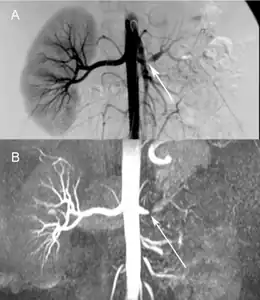

Comparison a) Digital subtraction arteriography and b) Unenhanced Magnetic resonance angiography of suboclusive left renal artery stenosis arrows -